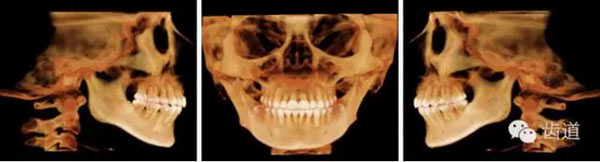

下頜后縮為主要特征的骨性II類,高角,前牙開(kāi)合,上前牙略唇傾,雙側(cè)下頜升支及髁狀突不對(duì)稱,右側(cè)較左側(cè)粗壯,左側(cè)髁狀突外斜面曾有吸收,但現(xiàn)骨白線與皮質(zhì)骨已比較連續(xù),上呼吸道正常。上

頜第三磨牙牙冠較小。

顏面軟組織:面部左右不對(duì)稱,頦部右偏,凸面型,上下唇較厚、略前突,鼻唇角較小,頦唇溝淺,下頜后縮,頦肌緊張,頦部形態(tài)不良

治療后CBCT

治療后關(guān)節(jié)截圖(CBCT)

治療后氣道截圖(CBCT)